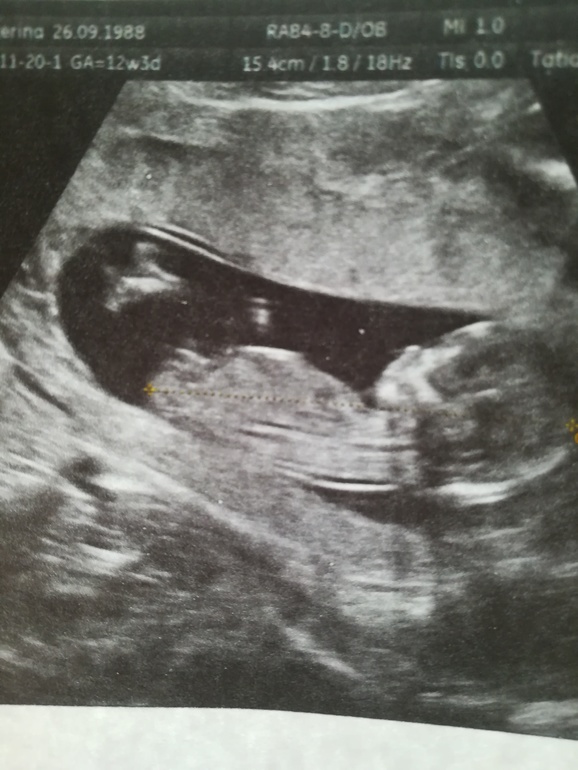

14,5 недель